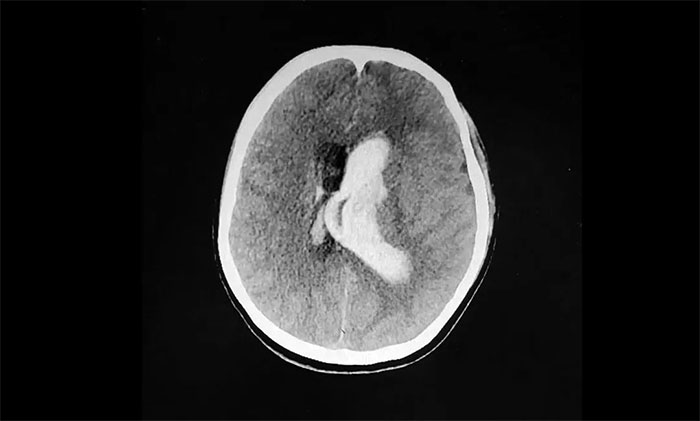

情急之下,家人匆忙將她送到附近醫(yī)院。經(jīng)頭顱CT檢查顯示:腦室出血,左側(cè)腦室、三、四腦室鑄型。

▲ 突發(fā)性腦出血,左側(cè)血腫已突入腦室

腦出血往往起病突然,進(jìn)展迅速。病情與出血部位、出血量及并發(fā)癥有關(guān),致死率很高,急性期為30%-40%。而腦室出血鑄型為腦出血中重癥類型,其往往出血量大,位置深在,病情危急,病死率相當(dāng)高。